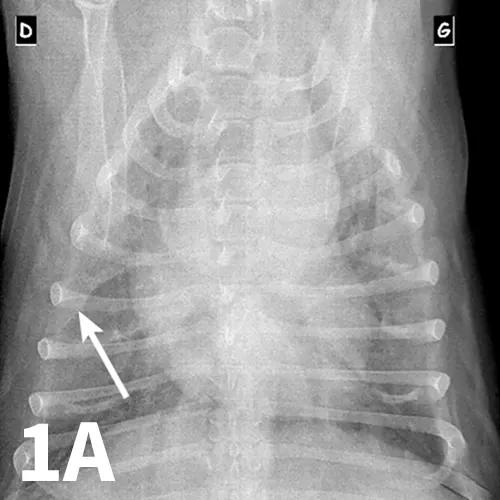

Ventrodorsal (A) and left and right lateral (B, C) thoracic radiographs of a 10-year-old West Highland white terrier showing a redundant tracheal membrane (1B, arrowhead; 1C, arrowhead), a severe generalized bronchointerstitial pattern, and a pleural fissure line (1A, arrow) between right pulmonary lobes.

Serum chemistry panel and CBC results were within range except for alkaline phosphatase (280 IU/L; range, 27-74) and hematocrit (57%; range, 37%-55%). Thoracic radiographs showed a severe bronchointerstitial pattern, right cardiomegaly, and prominent pulmonary artery trunk (Figure 1).